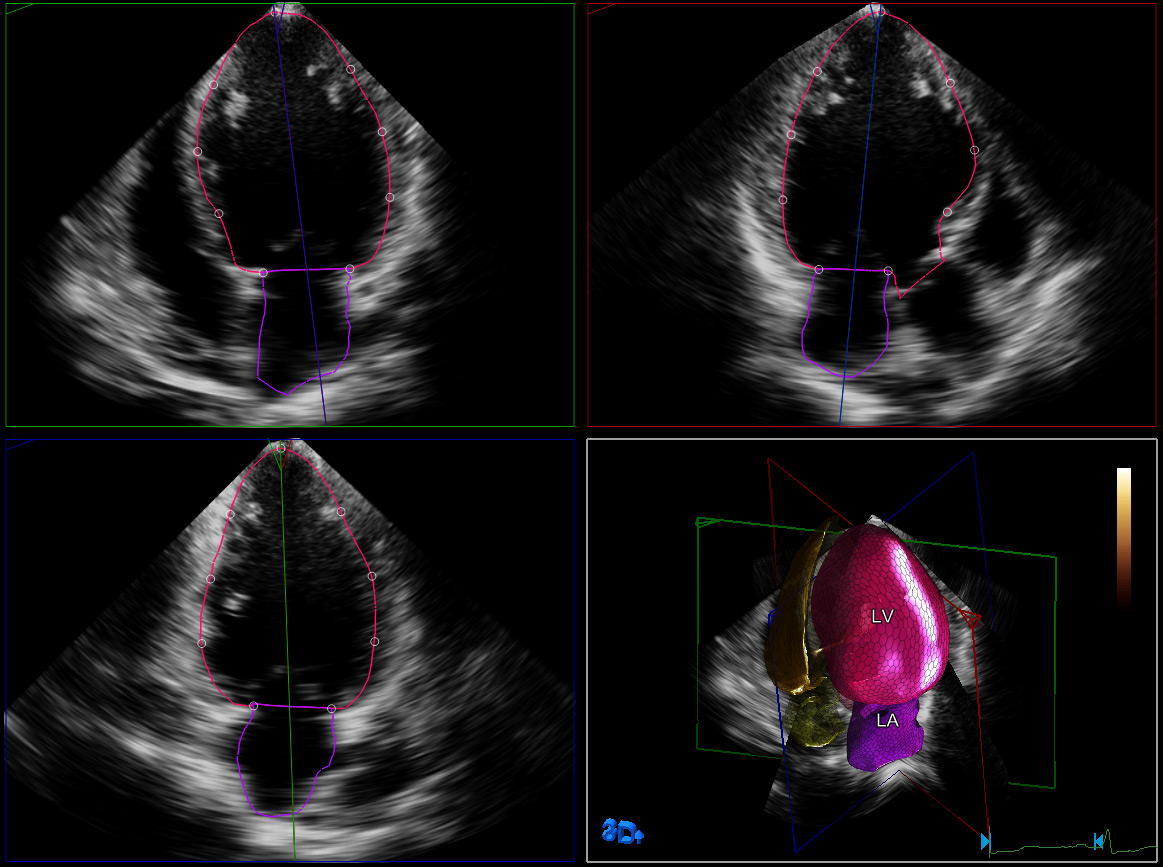

HeartModelA.I. es una herramienta 3D que puede ofrecer fracción de eyección (FE) reproducible robusta en solo unos segundos. Esta aplicación intuitiva y validada está diseñada para entregar la confianza de una cuantificación cardíaca que se adapta al flujo de trabajo cotidiano. HeartModelA.I. ofrece cuantificación 3D sencilla y rápida de la cámara cardíaca, mientras computa simultáneamente los volúmenes del ventrículo izquierdo (VI) y la aurícula izquierda (AI) desde un único bucle de volumen. HeartModelA.I. además de ofrecer cuantificación del VI, es la única herramienta validada para proporcionar volúmenes de la aurícula izquierda. Permite la caracterización sencilla del volumen de la AI para obtener más información clínica, sin tiempo ni pasos adicionales. Se ha demostrado que el volumen de la AI es un indicador de resultados cardiovasculares.

El estudio multicéntrico de Medvedofsky et al demuestra que la ecocardiografía 3-D con HeartModelA.I. es exacta y reproducible.

El estudio reciente de Tsang et al confirma los beneficios de HM en la cuantificación cardíaca izquierda.

HeartModelA.I. puede superar las limitaciones de una ecocardiografía 3D manual, según lo muestra un estudio reciente de Takeuchi et al.